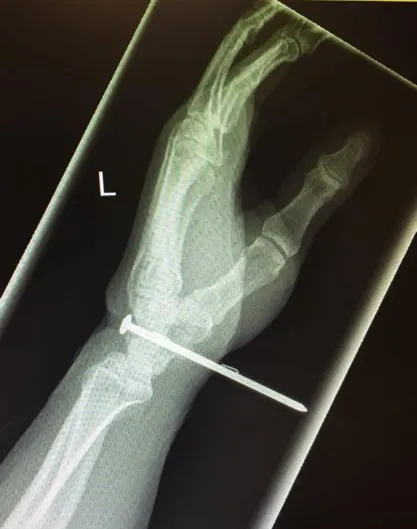

Abb. 3: 33-jähriger Schreiner, der während seiner Arbeitsjahre schon zahlreiche Arbeitsunfälle erlitten hat, im vorliegenden Fall sich versehentlich einen großen Nagel durch die Handwurzel getrieben hat. Der Fall wird nicht aurachirurgisch behandelt, sondern nach herkömmlichem Verfahren in der unfallchirurgischen Fachabteilung eines Krankenhauses. Man sieht: Vieles, aber keineswegs alles geht mit Aurachirurgie, v.a. wenn der Befund nicht feinstofflicher, sondern eher „grobstofflicher Natur“ ist. Allerdings zeigt sich nach operativer Entfernung des Nagels über Wochen noch eine deutliche Schmerzsymptomatik mit eingeschränkter Beweglichkeit im Handgelenk, was schließlich dann doch noch aurachirurgisch erfolgreich behandelt werden kann. Die Schmerzsymptomatik verschwindet binnen weniger Tage. Und tatsächlich bleibt er die Jahre nach dem Ereignis und nach aurachirurgischer Umprogrammierung unfallfrei, genauso wie die junge Frau mit dem Rohrreiniger.